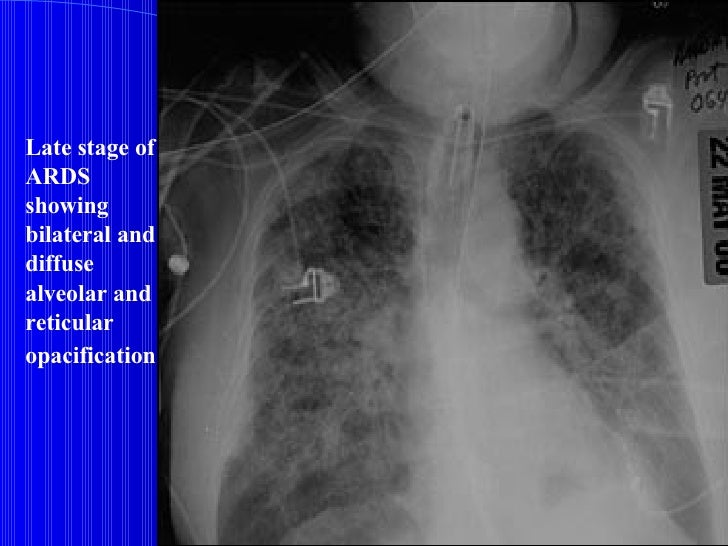

After 12 days’ administration of mezlocillin, the patient still had occasional chest pain and a repeated CT scan revealed recurrence of patchy opacification in the right lower lobe. Chest computed tomography (CT) scan presenting as pulmonary migratory infiltrates (PMI).